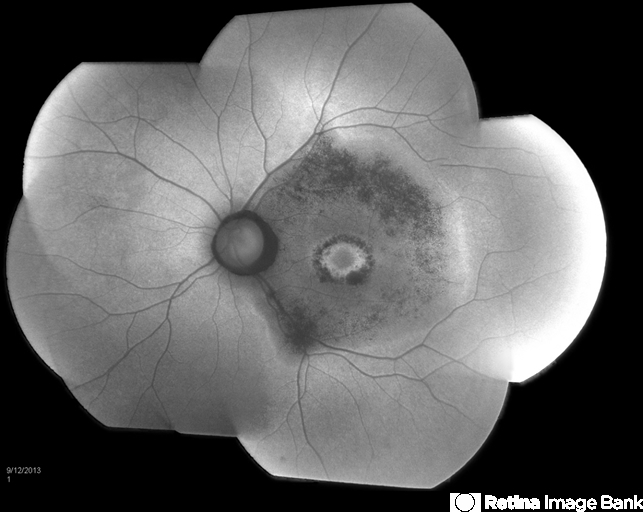

- Bulls Eye Maculopathy Without Plaquinel

- chorioretinal atrophy, maculopathy

- Fundus photograph reveals Bull's eye maculopathy without the use of plaquinel. Patient's VA is 20/20, right eye and 20/25, left eye. There are reported cases of Scleroderma patients with retinal pigment epithelial atrophy. Will return for follow up in 6-months.